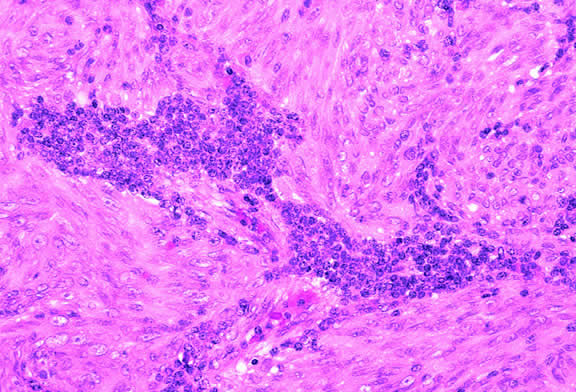

Lymphocytic infiltration of the tumor is one facet of the host response that can be assessed during the routine histopathologic examination (Fig. 47). In most parts of the body, a lymphocytic response to a malignant tumor generally is associated with an improved prognosis. In uveal melanoma, however, the presence of tumor infiltrating lymphocytes is associated with decreased survival.171 De la Cruz and coworkers used light microscopy to examine 1078 cases of uveal melanoma with known survival and found that 12.4% harbored 100 or more lymphocytes per 20 high-power (× 400) microscopic fields. The survival rate at 15 years was 36.7% for patients in the high lymphocytic group and 69.6% for patients in the low lymphocytic group. This seemingly counterintuitive observation is explained by the fact that extraocular dissemination of tumor cells is a requisite for stimulation of a T lymphocyte-mediated immune response. Ocular antigens are processed primarily in the spleen because the eye lacks lymphatics. Using immunohistochemistry, Whelchel and colleagues172 confirmed that lymphocytic infiltration is associated with death from metastasis and showed that T lymphocytes were the predominant cell type in about three fourths of the tumors.

Fig. 47. Uveal melanoma with prominent focus of lymphocytic infiltration. The presence of tumor infiltrating lymphocytes in uveal melanoma is associated with decreased survival. (Hematoxylin-eosin, × 100.)